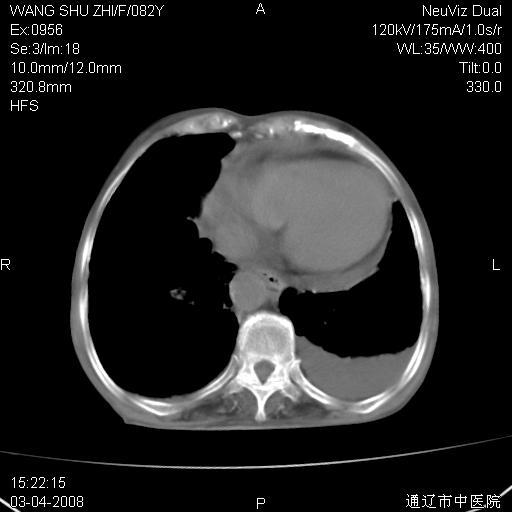

该患者为女性,82岁,既往肺心病、心衰病史。上纵隔影增宽,是否为畸形扩张的血管呢?因该患者年龄太大,又有较严重心脏病,故不适宜做增强检查。

中纵隔肿块最多见是淋巴瘤,而且以hd为多见,呈侵袭性生长,纵隔脂肪间隙消失,再加上心包和双侧胸腔积液,考虑为淋巴瘤(hd)应该说比较准确的。至于说是畸形的血管可能性小,因为畸形血管周围脂肪间隙应该存在。

纵隔淋巴结转移或淋巴瘤;双侧胸腔积液,心包积液。肺窗呢?

年龄如此之大暂不考虑淋巴瘤。资料未传完,考虑肺癌淋巴结转移,胸膜及心包转移。

左侧腋窝及纵隔内见多个肿大淋巴结影,左侧少量胸腔积液,心包积液,支持淋巴瘤可能性大,不除外淋巴结转移。

纵隔淋巴结转移或淋巴瘤;双侧胸腔积液,心包积液,建议进一步检查。